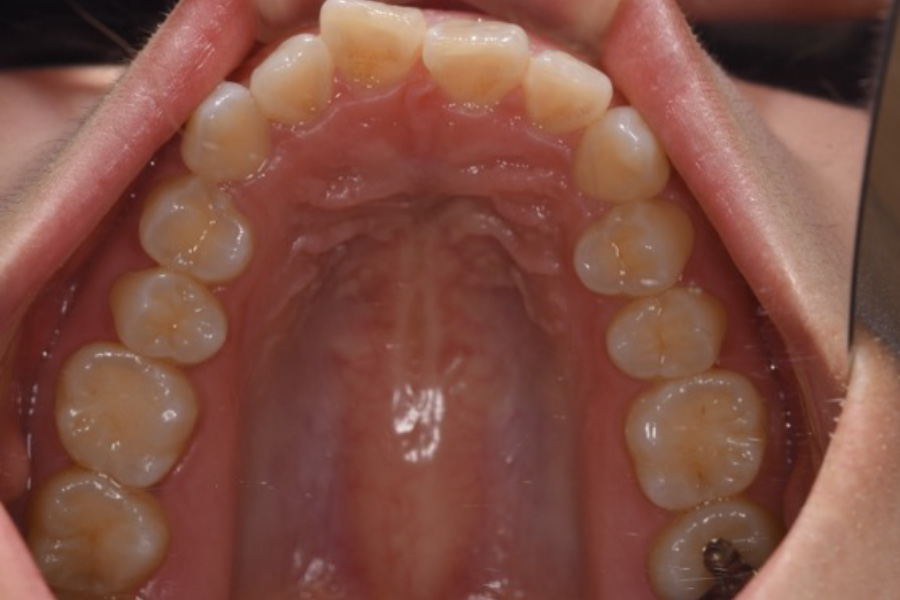

治療前

主訴 歯並びを治したい

期間 5か月

費用 マウスピース矯正(キャンペーン)

434,000円(税込)

治療内容 目立ちにくいマウスピース矯正(非抜歯矯正)

歯と歯の間に隙間をつくることにより、歯列弓を広げながら治療を行いました。